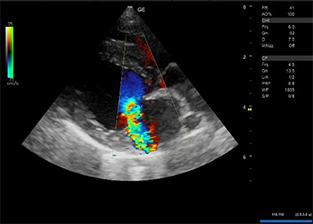

明らかな腹水貯留は認められなかった。 - 心エコー図検査にて、僧帽弁の逸脱とそれに伴う僧帽弁逆流が認められた。

- 以上から心原性肺水腫と診断した。